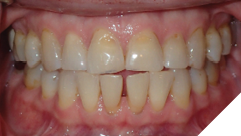

The majority of the orthodontic practices offer a period of “supervised retention” to their patients and communicates the customized retention recommendation with the patient’s general dentists. It is extremely important to work as a team to achieve long term clinical success in maintaining a functional bite and aesthetic smile. The general dentists continue to see their patients on a regular basis and have an opportunity to assess the orthodontic retainers and the bite after the supervised retention period is completed by the orthodontists. With great care, orthodontic retainers would serve for a long time (Fig. 1) without any major issues. However, in some cases, the failure to notice the clinical problems early on results in functional issues that would require a comprehensive orthodontic treatment to correct it (Fig. 2).

Fig. 2A

Fig. 2B

Fig. 2C